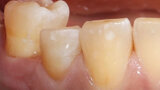

Fig. 14. Resultado: integración altamente estética de la restauración durante la revisión al cabo de seis meses.